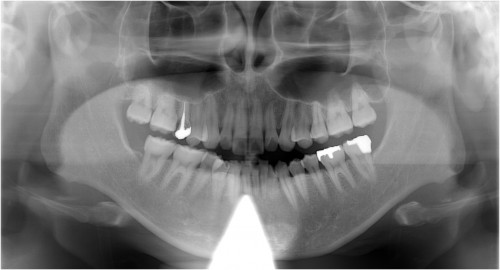

事故により左上34脱落→インプラント埋入

同拡大像

埋入後拡大像

川口で精密インプラント治療なら さかえ歯科クリニック